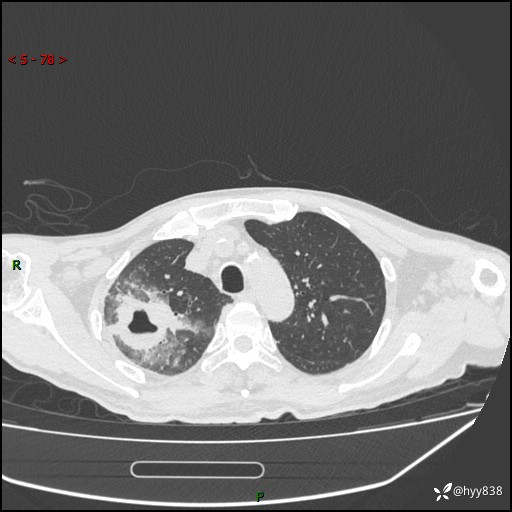

第一次胸部CT检查